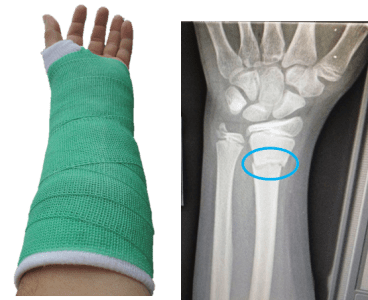

Extreme sports carry an element of risk and snowboarding is no exception. Wrist fractures are the most common injury amongst snowboarders, with an estimated 95,000 wrist fractures worldwide every year. As both feet are fixed to the board with bindings, a moment of instability can make it very difficult to regain balance. The instinct is to throw out arms to break the fall and protect the head and torso. This impact can result in a compressive load through the carpals and hyperextension in the wrist joint resulting in a fracture.

These injuries are particularly common amongst beginners and adolescents, who are learning the sport for the first time and struggling to stay on their feet. Elite performers are also susceptible to this type of injury, due to travelling at high speeds and performing dangerous tricks, as was the case with Katie who slipped off a rail.